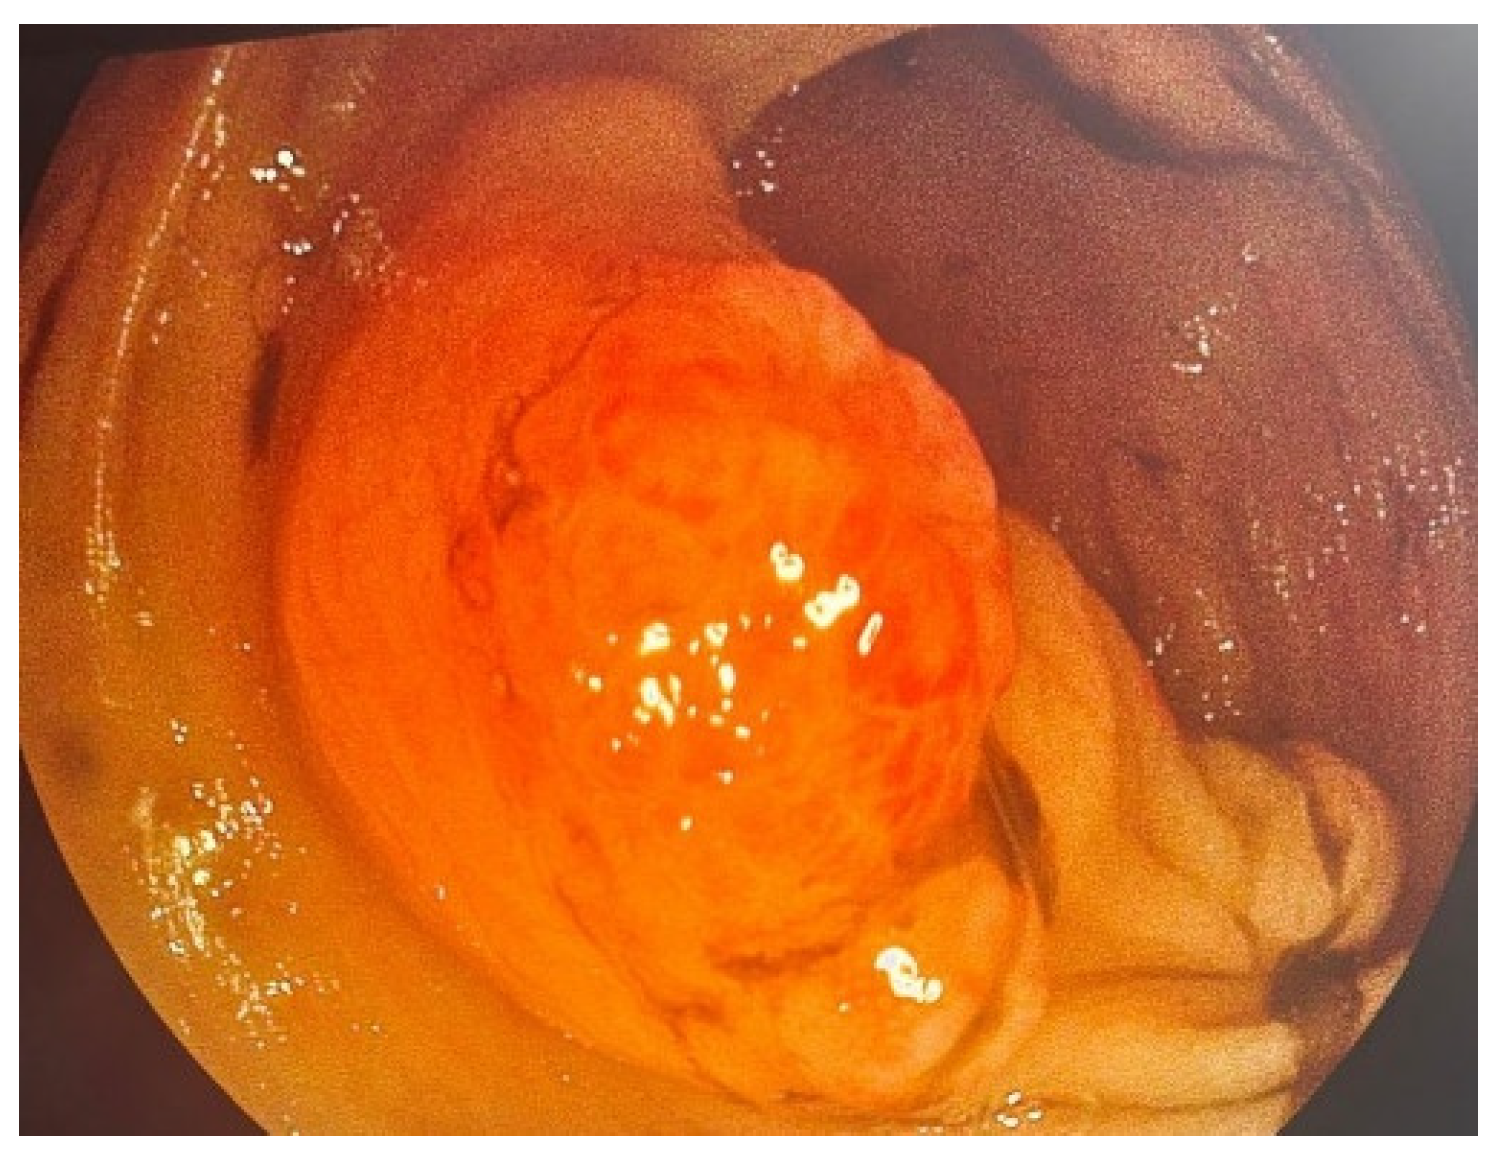

2. Case Presentation